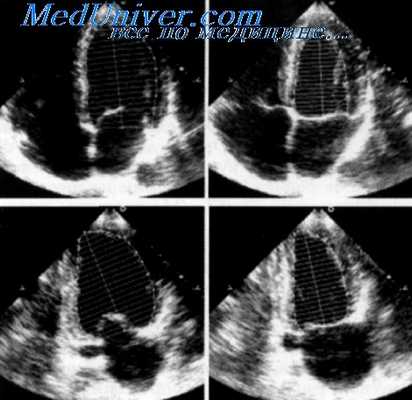

Видео. Концентрическая гипертрофия стенки левого желудочка при артериальной гипертензии. ЭхоКГ в плоскости четырех камер сердца из верхушечной позиции датчика.